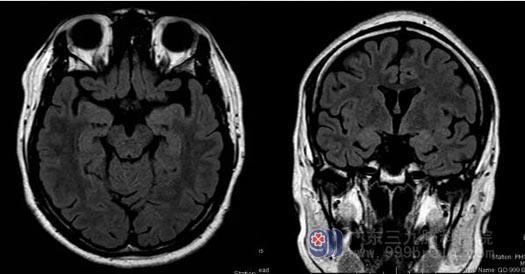

经过检查,李花发现小文左侧颞叶内侧局灶性脑皮质发育不良,幕上轻度弥漫性脑萎缩。颞叶病变很容易引起癫痫的发作。随后的长程视频脑电图也显示小文左后头部有癫痫样放电。最终李花明确诊断,小文是癫痫。

▲患者核磁共振检查